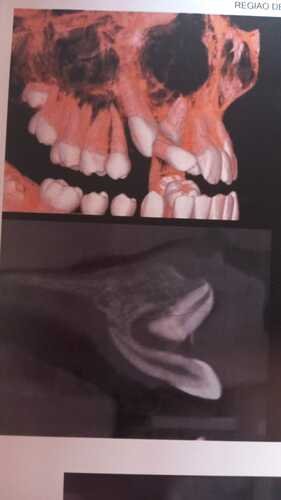

O nosso médico solicitou com urgência a intervenção cirúrgica por está em momento muito delicado do tratamento, onde vários dentes se encontram em cima um do outro e correndo riscos de nascerem dentes no céu da boca.

Hoje o Mateus se encontra com bastante dificuldade na dicção das palavras e dores faciais que comprometem sua audição…